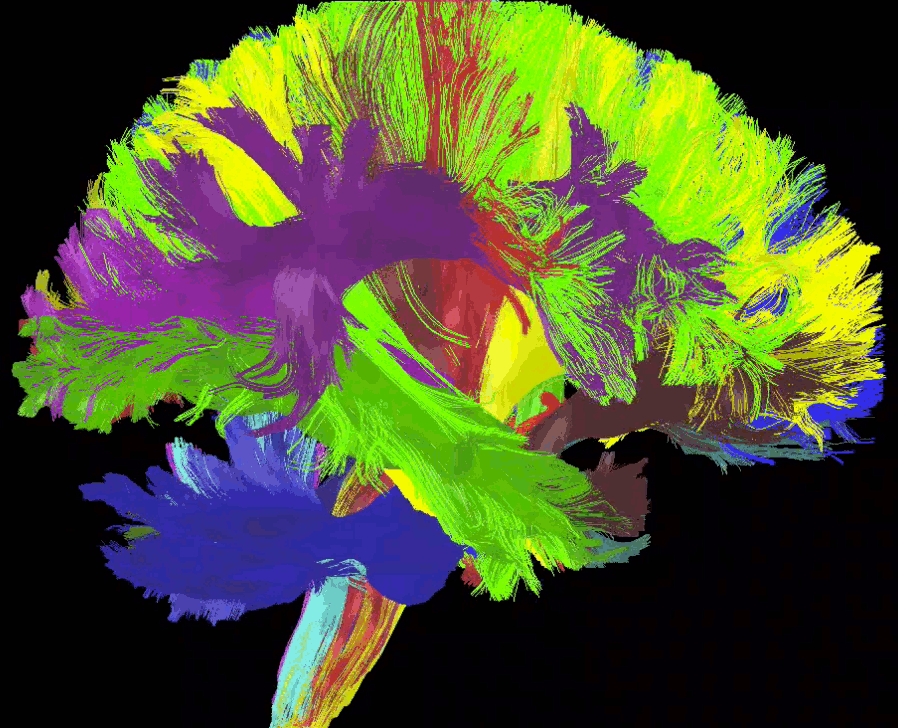

Streamlines reconstruction

- Tractography, fODF, tensors

- Fibernavigator

- MRview